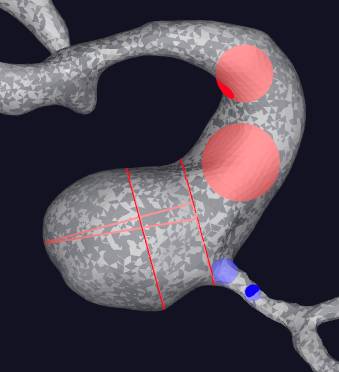

术前影像学资料(Aneu-Flow®形态学)

CS动脉瘤形态学参数定义示意图

重构模型

动脉瘤形态学参数

壁面剪切应力

振荡剪切因子

相对滞留时间

VD 参数释义:

WSS:壁面剪应力,表示血流作用于血管壁而产生的切向作用力。颜⾊越红,血流作用于血管内壁的摩擦力越大。

OSI:振荡剪切因子,表示WSS方向变化在心动周期中对血管壁的作用。颜⾊越红,WSS方向变化越大。

RRT:相对滞留时间,表示血流在血管壁附近的停滞时间。颜⾊越红,血流停滞时间越长。

RFV(V=0.1m/s)

Velocity(m/s)

PR

参数释义:

Velocity:血流速度,血流在单位时间内通过血管的距离。流线表示动脉瘤及载瘤动脉位置速度流线变化。颜⾊越红,流速越快。

RFV:残余血流体积,表示动脉瘤及载瘤动脉内速度大于等于某一定值的血流流动状态。

PR:血流储备分数,表示狭窄血管远端与近端压力的比值,反映狭窄所带来的压力损失。

2.可行性:术前完善高分辨磁共振、DSA以及血流动力学,结合患者病情制定合理手术策略;

3.安全性:术前经血流动力学与形态学充分评估动脉瘤应力情况与破裂风险,结合患者病情综合考量选择同期治疗狭窄与动脉瘤;